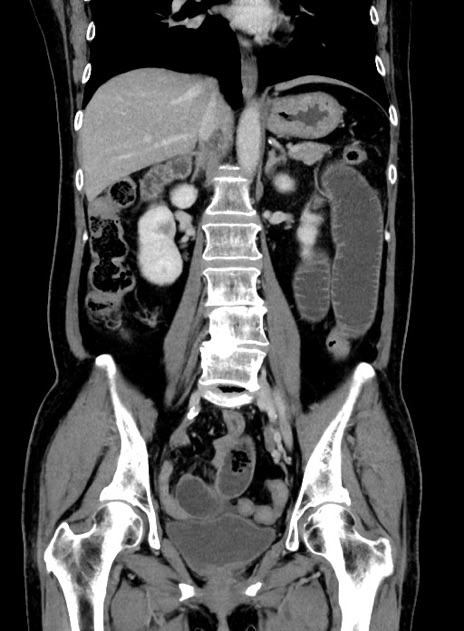

症例9(冠状断像)

【症例】 60歳代女性

【主訴】むかつき、みぞおちの痛み

【現病歴】3日前よりむかつきがあり、食事がとれない。

【既往歴】糖尿病

【身体所見】発熱なし、心窩部圧痛軽度あるも、腹膜刺激症状なし。

【データ】WBC 7400、CRP 1.92